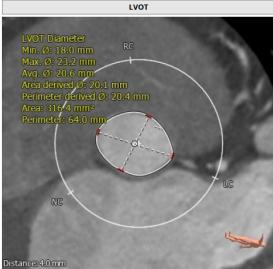

CT:

主动脉瓣Type 0型二叶瓣,瓣叶瓣缘结节样增厚伴中度钙化,开放受限。冠脉高度可。法式窦结构可,心脏角度约52°,左室较小,升主动脉未见明显扩张,右股动脉直径大于5.5mm,可作为主入路。患者为中度钙化的,重度主动脉瓣狭窄,呈鱼嘴型,结合主动脉根部结构,考虑植入Sapien 3瓣膜。

主动脉瓣环

左室流出道